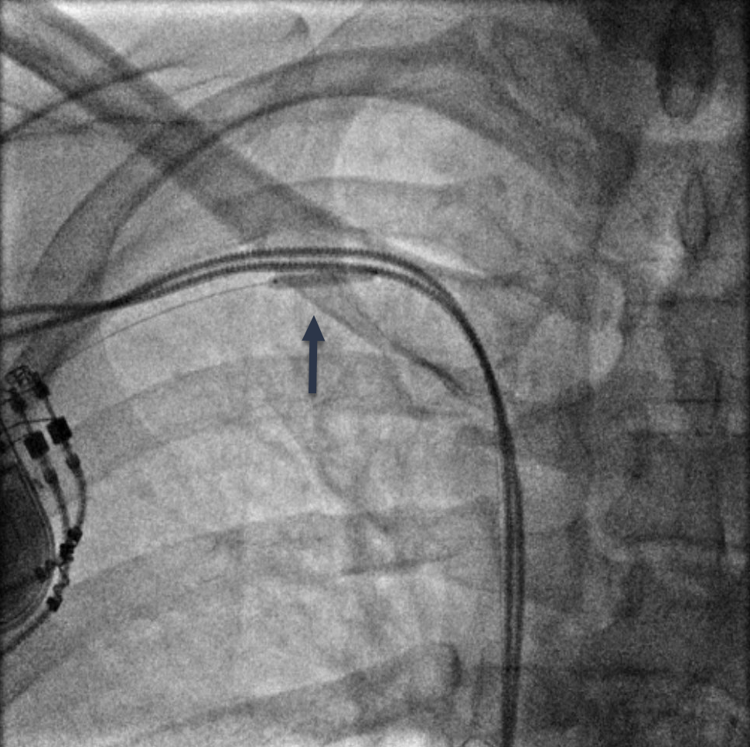

RHC procedure. Arm venous access was obtained with ultrasound guidance in all cases. After successful ‘radial’ sheath insertion, a 5-French (Fr) or 6-Fr balloon flotation right heart catheter was advanced (either by itself or over a 0.014-inch coronary guidewire based on operator preference) through the sheath and then into the pulmonary artery (PA). If resistance to catheter passage was encountered, a venogram (Figures 1A, 2A, and 3A) was performed using diluted contrast (50% saline) to determine the venous anatomy, the location, and the extent of stenosis, and to guide further wire/catheter advancement. In some cases, using different guidewires or catheters (eg, downsizing a 6 Fr to a 5 Fr) allowed RHC success. When a 0.014-inch wire was advanced into the superior vena cava (SVC) and the passage of a balloon-tip right heart catheter over the wire was unsuccessful due to a stenosis and/or pacemaker/ICD wires, a coronary balloon or 0.014-inch compatible peripheral balloon was then advanced over the wire and dilatation of the stenosis was performed (Figures 1B, 2B, and 3B). In some cases, a single balloon dilatation allowed passage of the RHC catheter. In others, a progressive increase in balloon diameters was needed. At the end of the procedure, the venous sheath was withdrawn, and manual compression was applied to the puncture site until hemostasis was attained.

We were able to pass a guidewire through all stenoses. A coronary or peripheral balloon catheter was then passed over the guidewire, and dilatation was performed (Figures 1B, 2B, and 3B). Coronary angioplasty balloons were utilized in 8 (44.4%), peripheral balloons in 7 (38.9%), and both peripheral and coronary balloons in 3 patients (16.7%). The balloons used were predominantly non-compliant (83.3%). Eleven patients (61.1%) required only a single balloon for successful venoplasty, while 7 patients (38.9%) had at least 2 balloons used, upsizing from the previously used balloon. The balloons' median diameter and length were 4 mm (range, 3-4 mm) and 60 mm (range, 20-200 mm), respectively. The median highest inflation pressure used was 14 atm (range, 8-18). After SVS dilatation, we performed successful RHC in 100% of the cases with a catheter passed into the PA. The average length of the procedure for successful RHC was 35.2 ± 15.5 minutes. There were no complications at the end of the procedure in any of our patients.

Subclavian venoplasty is recognized by the Heart Rhythm Society Expert Consensus Statement as a safe and reliable procedure when venous stenoses hinder central venous access.19 One study included 130 patients who underwent percutaneous subclavian venoplasty (PSV) for lead-related subclavian vein stenoses.5 In patients with wire refractory obstruction, mechanical (microdissection) or power (laser or radiofrequency) assistance was utilized. In this study, PSV was not associated with any significant complication. Minor complications did occur, including balloon rupture with contrast extravasation in 3 patients, but there were no reported clinical implications. Our small single-center experience also demonstrated that subclavian vein balloon venoplasty is practical, effective, and safe. We purposely used balloon diameters (3-4 mm) that were significantly smaller than the diameter of the subclavian vein (10-20 mm) to prevent vein injury/perforation. Earlier in our experience, we would often initially perform venoplasty with a 3-mm diameter balloon. More than one-third of the time, a right heart catheter could not be passed in these cases, requiring subsequent dilatation with a larger 4-mm diameter balloon. Over time our technique evolved to initial use of 4-mm diameter balloons in most cases to improve the efficacy of venoplasty.